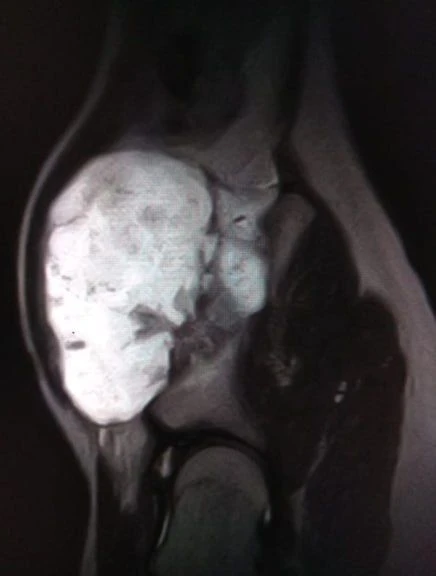

В областной детской клинической больнице №2 прооперировали подростка с редким диагнозом «экзостозная хондродисплазия». У мальчика образовался костно-хрящевой нарост на подвздошной кости размерами 12 на 9 на 7 сантиметров. Образование вызывало боль, мешало движению и угрожало тазобедренному суставу.